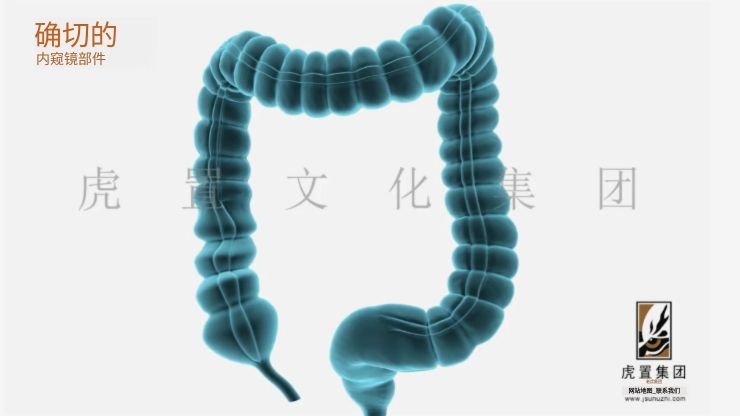

深耕于数字设计及展示领域的虎置文化集团成立20年,正努力成为全球知名的数字设计及展示服务商,为客户提供设计、展示及施工的一站式服务,为不同行业客户提供基于文化创意服务的整体解决方案。设计包括:建筑设计、景观设计、规划设计、展馆设计、室内设计、BIM设计;展示包括:三维动画、全息展示、影视广告、数字展馆、二维动漫、3D仿真效果图、VR&AR、企业宣传片等;施工包括:展馆展厅、室内装饰、幕墙工程、亮化工程。

公司依靠先进的三维动画制作技术,致力于三维动画的定制和制作,为数百家企业制作了各种类型的三维动画,有着丰富的实践经验和服务水平,制作的三维动画具有更灵活的表现形式、更强大的说服力和更生动的效果,成为众多企事业单位宣传产品、拓展市场、塑造品牌影响力的重要工具。服务政府、部队、世界五百强企业百余家;服务“一带一路”、“中国 制造2025”等重大国家战略项目;服务美国斯坦福、上海同济大学等国内外知名高校。